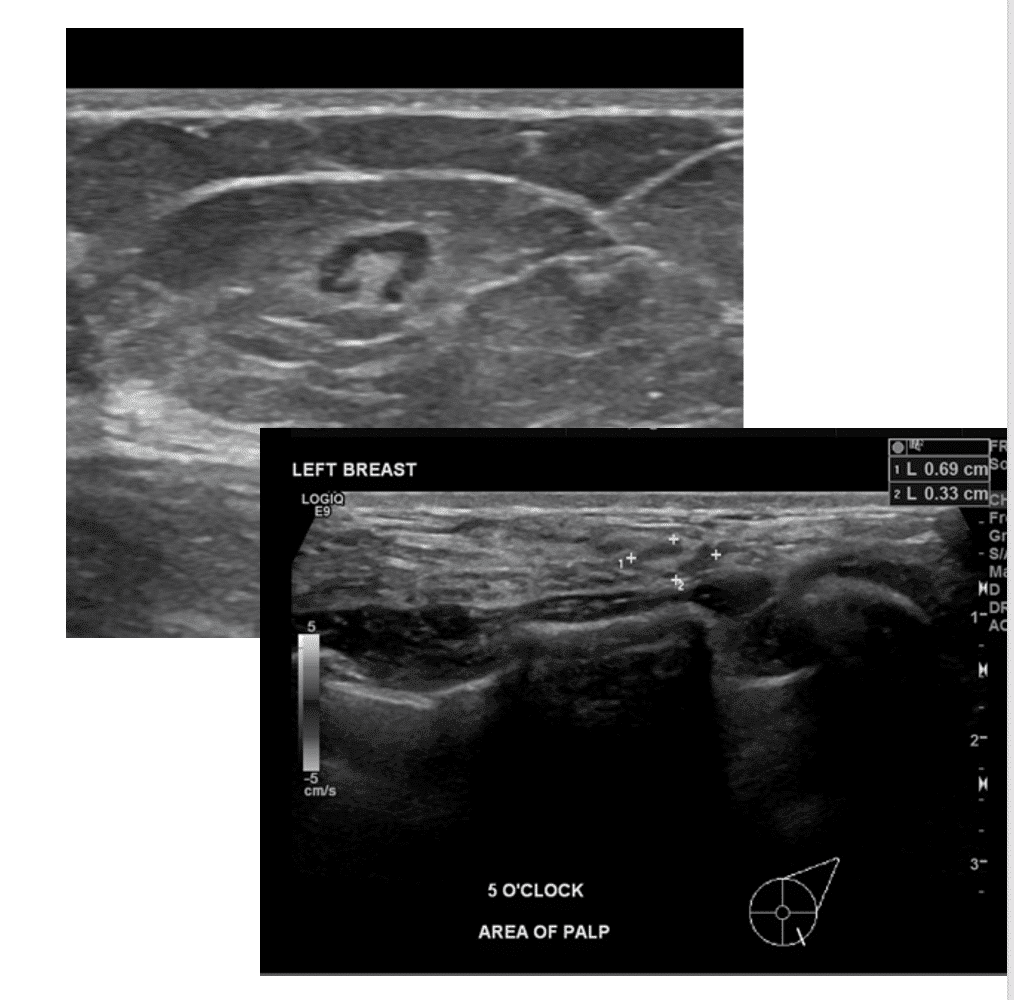

Lactating Adenoma

Lactating adenomas are benign (non-cancerous) masses comprised of dense glandular tissue and most commonly occur in the upper outer part of the breast. They can present during pregnancy or lactation and likely are related to hormonal stimulation. They may become large; however, they reduce in size as a woman progresses further in the postpartum period and eventually disappear when lactation is complete. They can appear similar to fibroadenoma on breast imaging, as smooth, oval lesions. Diagnosis can be confirmed with a core needle biopsy, but they do not require surgical excision.

Prominent lymph nodes are common during lactation, both in lymph nodes under the arm (axilla) or within the breast (intramammary lymph nodes), which often are noticed by thinner individuals with smaller breasts. Ultrasound and/or mammogram can be obtained to confirm benign appearance.